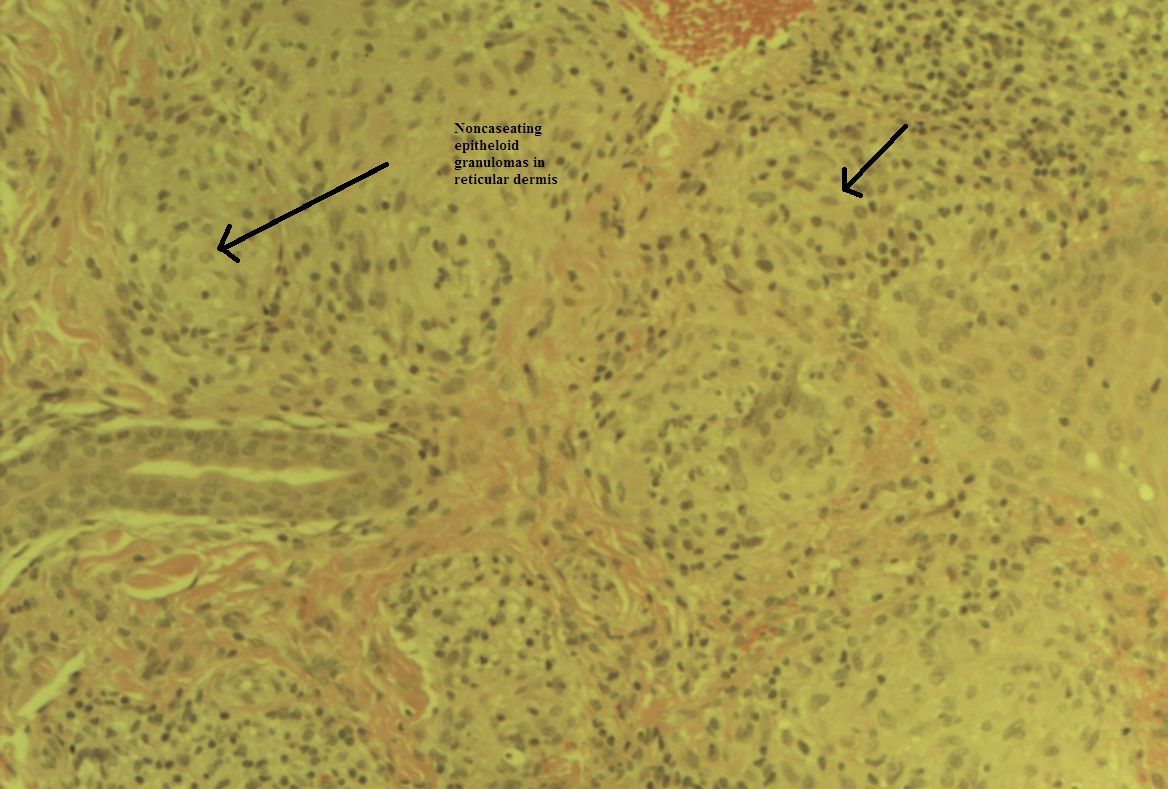

The patient’s ECG and echocardiogram results were unremarkable. Laboratory data were notable only for an elevated erythrocyte sedimentation rate of 60 mm/h (normal range, 0 to 20 mm/h). The rest of the workup-including complete blood cell count with differential; metabolic panel, with blood urea nitrogen, creatinine, glucose, electrolyte, and calcium levels; hepatic panel; antinuclear antibodies; rheumatoid factor; antineutrophil cytoplasmic antibodies; serum angiotensin converting enzyme levels; and urinalysis-was unremarkable. HIV and purified protein derivative test results were negative. Acid-fast bacilli test (Figure 4a) and Gram stain results (Figure 4b) were negative.

When skin biopsy findings from the rash around the patient’s eyes were considered in the context of chest images and PFT results, a diagnosis was made.

Answer: Pulmonary sarcoidosis. Positive findings of sarcoidosis involving the skin along with bilateral diffuse interstitial lung infiltrates and hilar lymphadenopathy supported a diagnosis of pulmonary sarcoidosis.